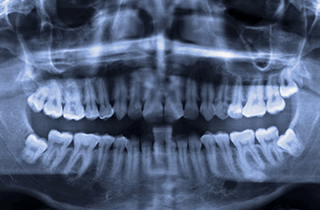

사랑니는 상하좌우에 한 개씩 총 4개의 치아로 구강 내 가장 뒤쪽에 위치하며 영구치 중 가장 늦게 나오는 어금니입니다. 보통 10대 후반에서 20대 초중반에 맹출되며, 현대인들은 사랑니가 아예 없거나 진화함에 따라 턱뼈의 크기가 작아져 사랑니가 잇몸 속에 묻혀 여러가지 구강 문제를 일으키기도 합니다.